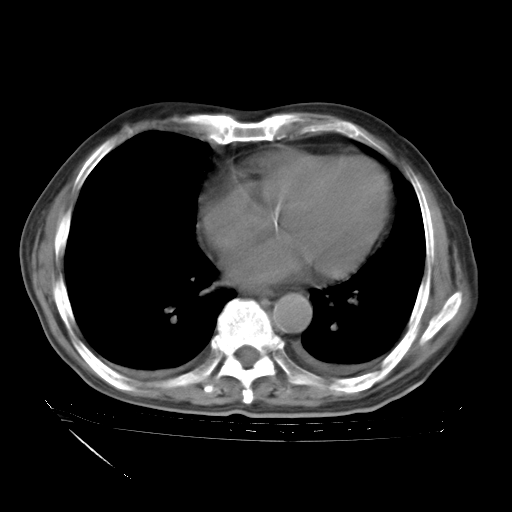

甲强龙80mg/日+抗结核治疗(异烟肼+利福霉素+乙胺丁醇)10天。复查肺部CT。

治疗10天肺部CT

补充下:5月9日胸部CT:似乎已见双下肺胸腔积液了,鉴于目前有下肢水肿,肝功示:白蛋白低,应注意多浆膜腔积液(漏出液可能大?),需注意!